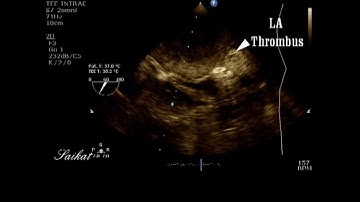

Detection of Left Atrial Appendage Thrombus by TEE